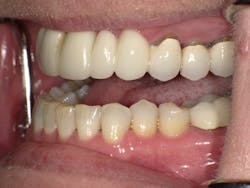

Left side prior to restorative treatment

Right side prior to restorative treatment; note the fractured bridge